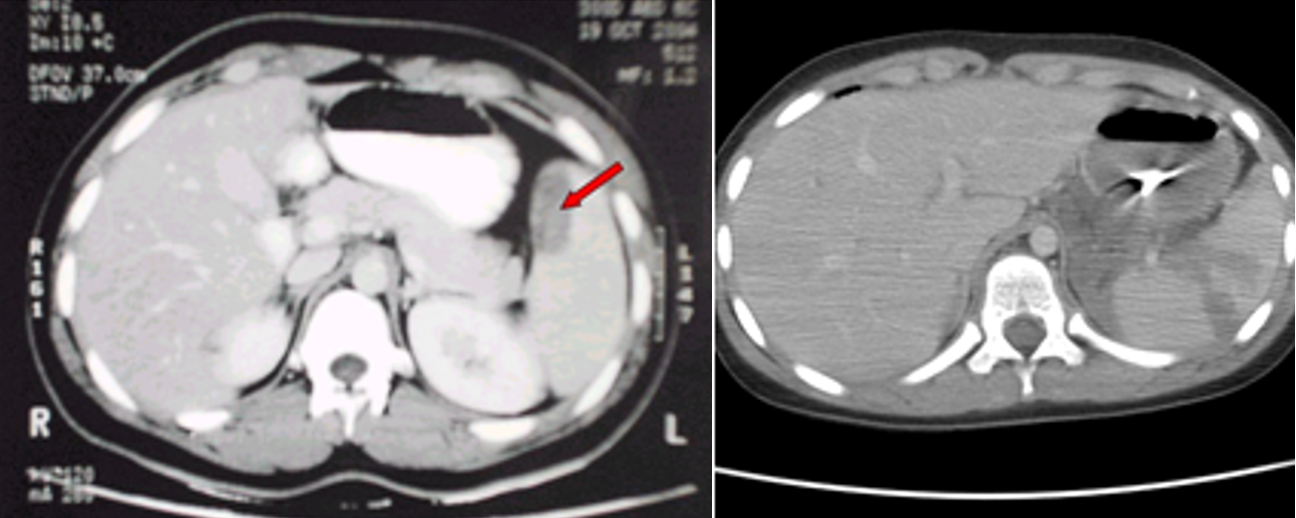

- CT in hemodynamically -stable patients

(Image: Splenic injury (CT scan))

- FAST, CT scan.

- FAST: splenic injury, free fluid (hemoperitoneum)